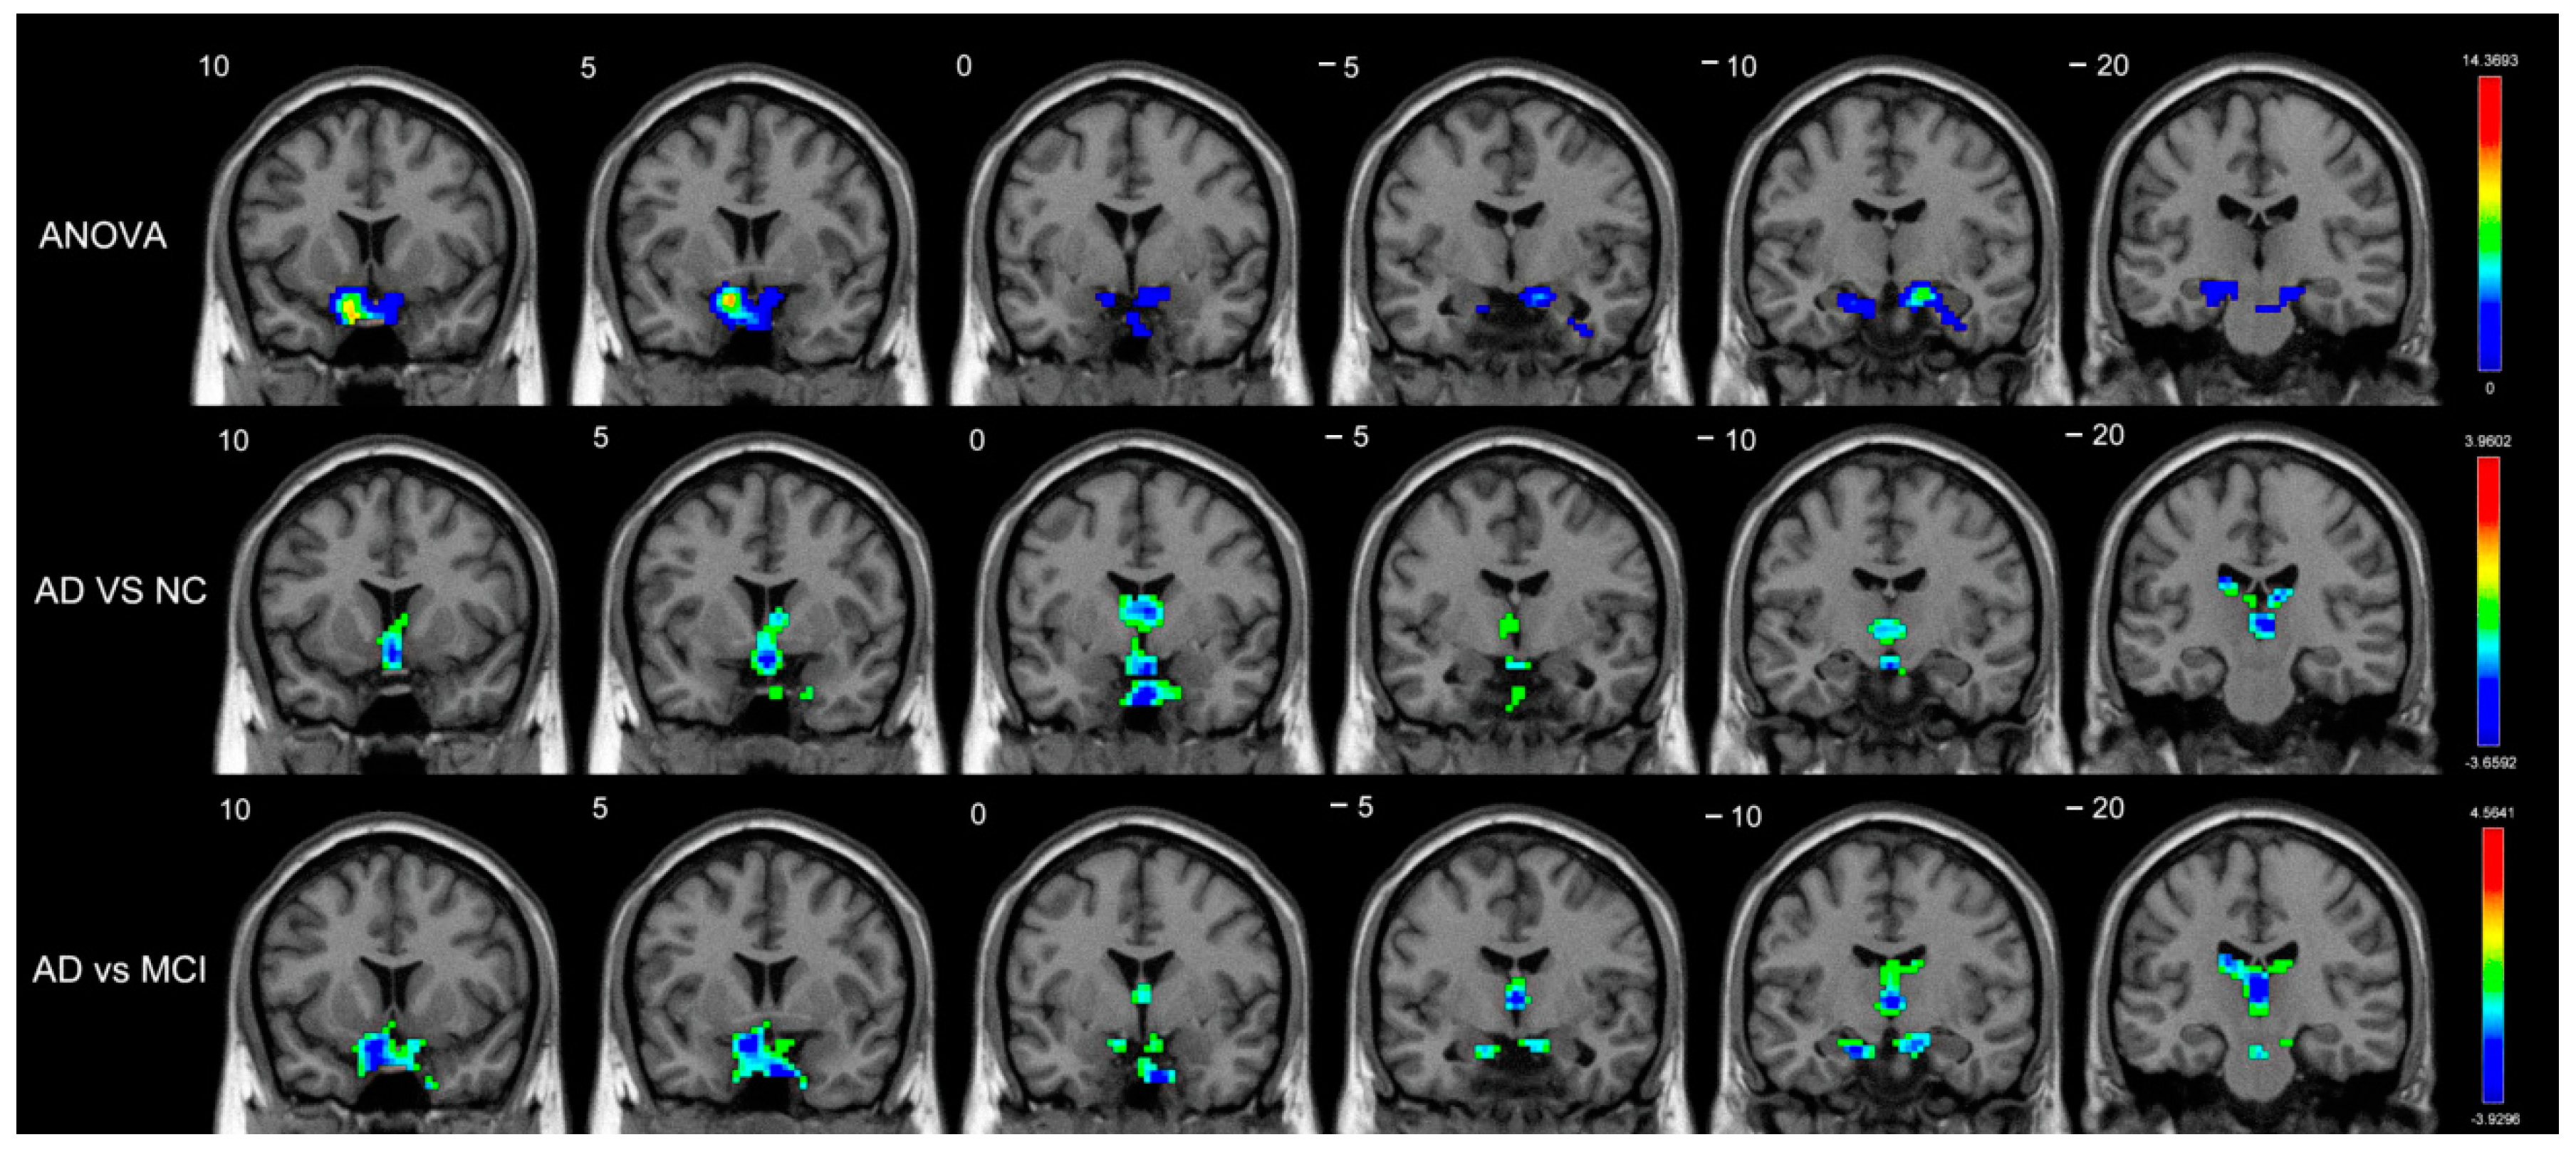

| ANOVA | |||||

| Short-range | Amygdala_R | BA34 | (18,0,−17) | 5.9018 | 3 |

| Long-range | Caudate_R | - | (18,−5,20) | 11.3438 | 66 |

| Caudate_L | - | (−16,−12,23) | 6.4713 | 43 | |

| Amygdala_R | BA34 | (19,1,−17) | 13.2933 | 32 | |

| Pallidum_R | BA48 | (19,0,−5) | 7.8705 | 14 | |

| Putamen_R | BA48 | (33,−9,0) | 6.1615 | 7 | |

| MCI vs. NC | |||||

| Long-range | Amygdala_R | BA34 | (21,−2,−17) | 4.4157 | 38 |

| Amygdala_L | - | (−13,2,−15) | 3.3582 | 6 | |

| Putamen_L | BA25 | (−14,7,−9) | 3.2804 | 7 | |

| Pallidum_R | BA25 | (12,3,−5) | 3.1270 | 5 | |

| AD vs. NC | |||||

| Short-range | Caudate_L | - | (−7,1,11) | −2.9712 | 29 |

| Caudate_R | - | (9,5,7) | −2.8622 | 8 | |

| AD vs. MCI | |||||

| Short-range | Caudate_L | - | (−18,−21,23) | −3.2570 | 9 |

| Caudate_R | - | (16,−18,21) | −2.8545 | 4 | |

| Long-range | Caudate_L | - | (−15,14,18) | −3.7649 | 66 |

| Caudate_R | - | (17,6,23) | −3.7601 | 54 | |

| Amygdala_R | BA48 | (19,2,−11) | −3.6551 | 20 | |

| Pallidum_R | BA48 | (19,−3,−2) | −3.4747 | 9 |